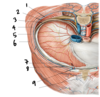

What is the neuromuscular bundle?

Where is it found?

The intercostal nerve, artery, and vein that belong to each intercostal space

The bundle sits in the costal groove, which is sheltered by the distal edge of the upper rib of the intercostal space

When you need to access the parietal pleura, why would you insert the needle just above the rib inferior to the intercostal space?

You want to avoid the neuromuscular bundle, which is associated with the rib superior to the intercostal space

Describe the path of an intercostal nerve

The intercostal nerve is a spinal nerve

Presynaptic: in CNS

Synapse: in sympathetic trunk

Postsynaptic: Leaves trunk, follows ventral ramus, innervates muscles in the thoracic body wall

Between which two layers of muscle would you find an intercostal nerve?

Between the internal and innermost intercostal muscles